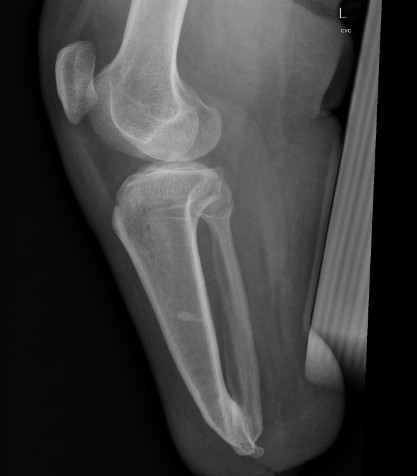

Syme's amputation

Concept

- ankle disarticulation

- remove talus and calcaneum

- remove both malleoli

- preserve heel pad

Technique

- incision from tip of lateral malleolus to medial malleolus across front of ankle

- then continue plantar under sole between same points / MT bases

- need to preserve large post heel pad

- excise talus & calcaneus

- remove malleoli at level of joint & contour

- divide arteries / veins / nerves above levels of flaps

- anchor heel pad to anterior tibia via intra-osseous sutures

Issues

- small surface area / risk of ulcers

- LLD of 4 - 7 cm

- custom AFO